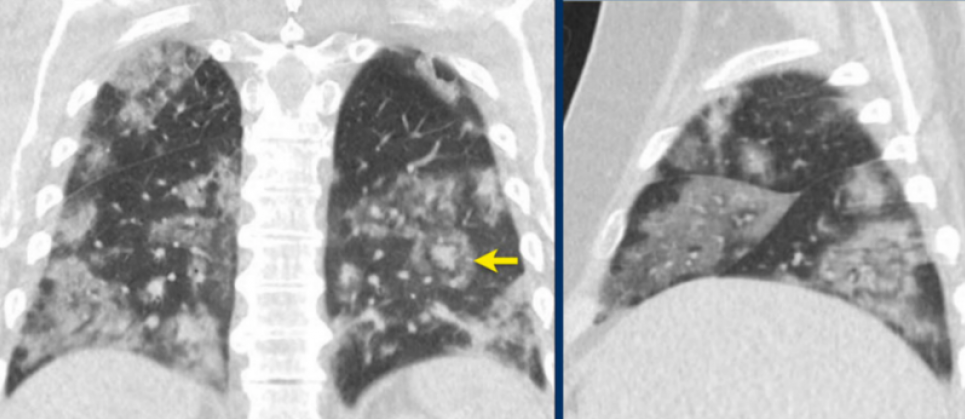

У всіх містах Україна зараз спостерігається паніка і тривога, люди стоять у чергах, щоб зробити комп'ютерну томографію легень (КТ). Всі бояться, що COVID-19 дасть ускладнення. Сімейний лікар Центру первинної медико-санітарної допомоги № 1 Оболонського району Києва Фелікс Ілясевич розповів, коли цю процедуру дійсно треба робити. Повідомляють "Факты".

"Не тільки лікарі призначають: багато пацієнтів роблять КТ самі, як тільки з'явився кашель. Але стан легенів, який показує КТ, часто не відповідає тяжкості хвороби. Наприклад, у моєї літньої пацієнтки не було навіть натяку на коронавірусну інфекцію, а КТ вона робила з іншої причини, але це дослідження виявило зміни, характерні для двосторонньої пневмонії", - розповів медик.

"Якщо симптоми зменшуються — не підвищується температура, зменшується кашель, сатурація в нормі, то робити КТ немає сенсу. Променеве навантаження при цьому дослідженні в кілька разів більше, ніж при звичайному рентгені", - розповів Фелікс Ілясевич.